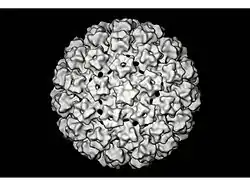

Papillomaviridae es una familia de virus que infectan vertebrados.[1][2][3] Además, se conocen más de 100 diferentes tipos de papilomavirus humanos (VPH). Tienen un genoma ADN bicatenario y por lo tanto pertenecen al Grupo I de la Clasificación de Baltimore. Su estructura se caracteriza por no presentar envoltura, la cápside es de simetría icosaédrica y mide unos 60 nm de diámetro.

Los virus del papiloma no presentan envoltura. Una sola proteína viral, denominada L1, es necesaria y suficiente para la formación de un cápside de 60 nm compuesta por 72 capsómeros con forma de estrella. Como la mayoría de los virus sin envoltura, la cápside es geométricamente regular y presentan simetría icosaédrica. Las partículas autoensambladas similares al virus compuestas de L1 son la base de un grupo de las vacunas profilácticas contra el virus, diseñados para generar anticuerpos neutralizantes del virus que protegen contra la infección inicial.